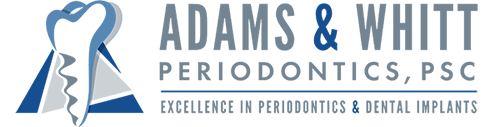

Frenectomy

Before